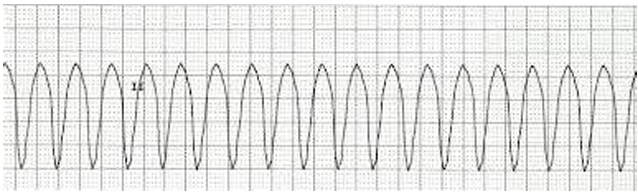

Uma paciente de 62 anos foi atendida em um hospital sem serviço de hemodinâmica, com um infarto agudo do miocárdio da parede inferior com supra de ST, sendo tratada com trombólise após um delta T de 6h. Evoluiu com melhora da dor, porém em Killip II. No segundo dia de internação na Unidade de Terapia Intensiva, apresentou palpitação e dor torácica, seguidas de perda da consciência e ausência de pulso carotídeo palpável.

O monitor registrou o seguinte traçado:

Nesse momento, a conduta imediata prioritária deverá ser de